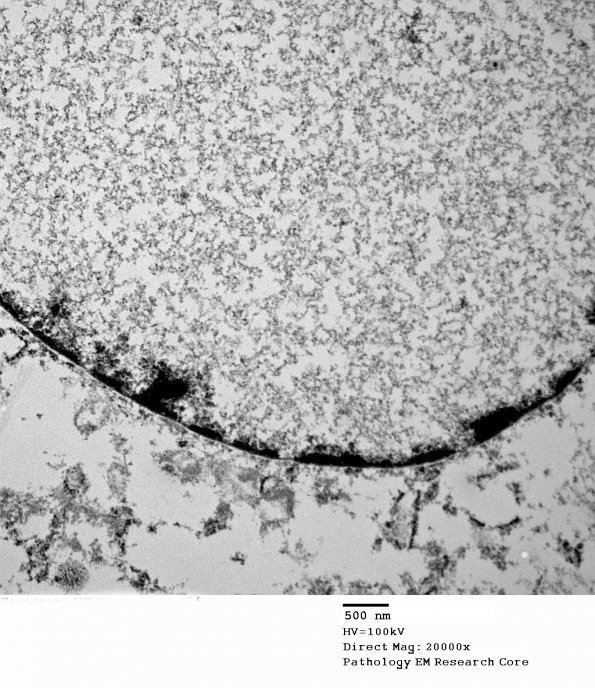

Notice the homogenous granular nucleoplasm but absence of virions (electron micrograph).